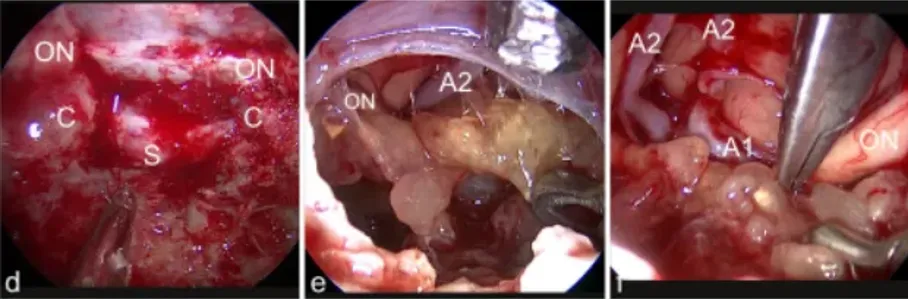

d图中,经鼻内镜手术入路暴露。视神经的隆起(ON)可以看到总颈动脉(C)和鞍状硬脑膜(S)。e图表示切除之后肿瘤隆起,肿瘤上表面暴露在30°内窥镜下观察。右前A2节段可见脑动脉和右视神经(ON)。f图中,从视交叉切开肿瘤,使用镊子双向牵拉分离暴露(视神经ON)、A1和前脑动脉的A2段(A1,A2)。

g图表示背侧肿瘤表面,垂体柄浸润(ST,在虚线)被可视化处理眼动脉(O),后交通动脉P1段(P)和后交通动脉(箭头)。h图表示肿瘤切除后,左视神经内出现严重的压迹(箭头),由于肿瘤对神经的压迫和A1区段引起的可以看到大脑前动脉(A1和A2)。i图中,最终检查显示垂体后叶浸润(ST)后部、交通动脉(箭头)、岩上段颈内动脉(C)和动眼神经(O)的肿瘤残留(T)